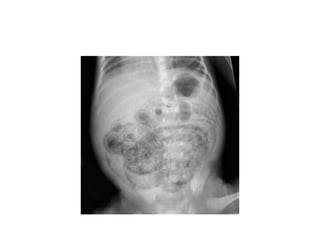

imaging

• Multiple gas filled loops of intestine

• Pneumatosis intestinalisc: pathognomonic for

NEC

• a collection of cystic or linear lucencies in the

bowel wall,

• Frequency may reach 19-98%but may be

absent in upto 14% of cases of NEC

imaging • Multiple gasfilled loops of intestine • Pneumatosis intestinalisc: pathognomonic for NEC • a collection of cystic or linear lucencies in the bowel wall, • Frequency may reach 19-98%but may be absent in upto 14% of cases of NEC

• 25.

• Portal venousgas: linear branching radiolucencies overlying the liver and often extending to its periphery • incidence of 10% to 30%.poor prognosis • Pneumoperitoneum: in 12-30% of patients • Best seen on lateral decubitus film • Football sign, double wall sign, • Only 63% of patients with perforation show the xray sign